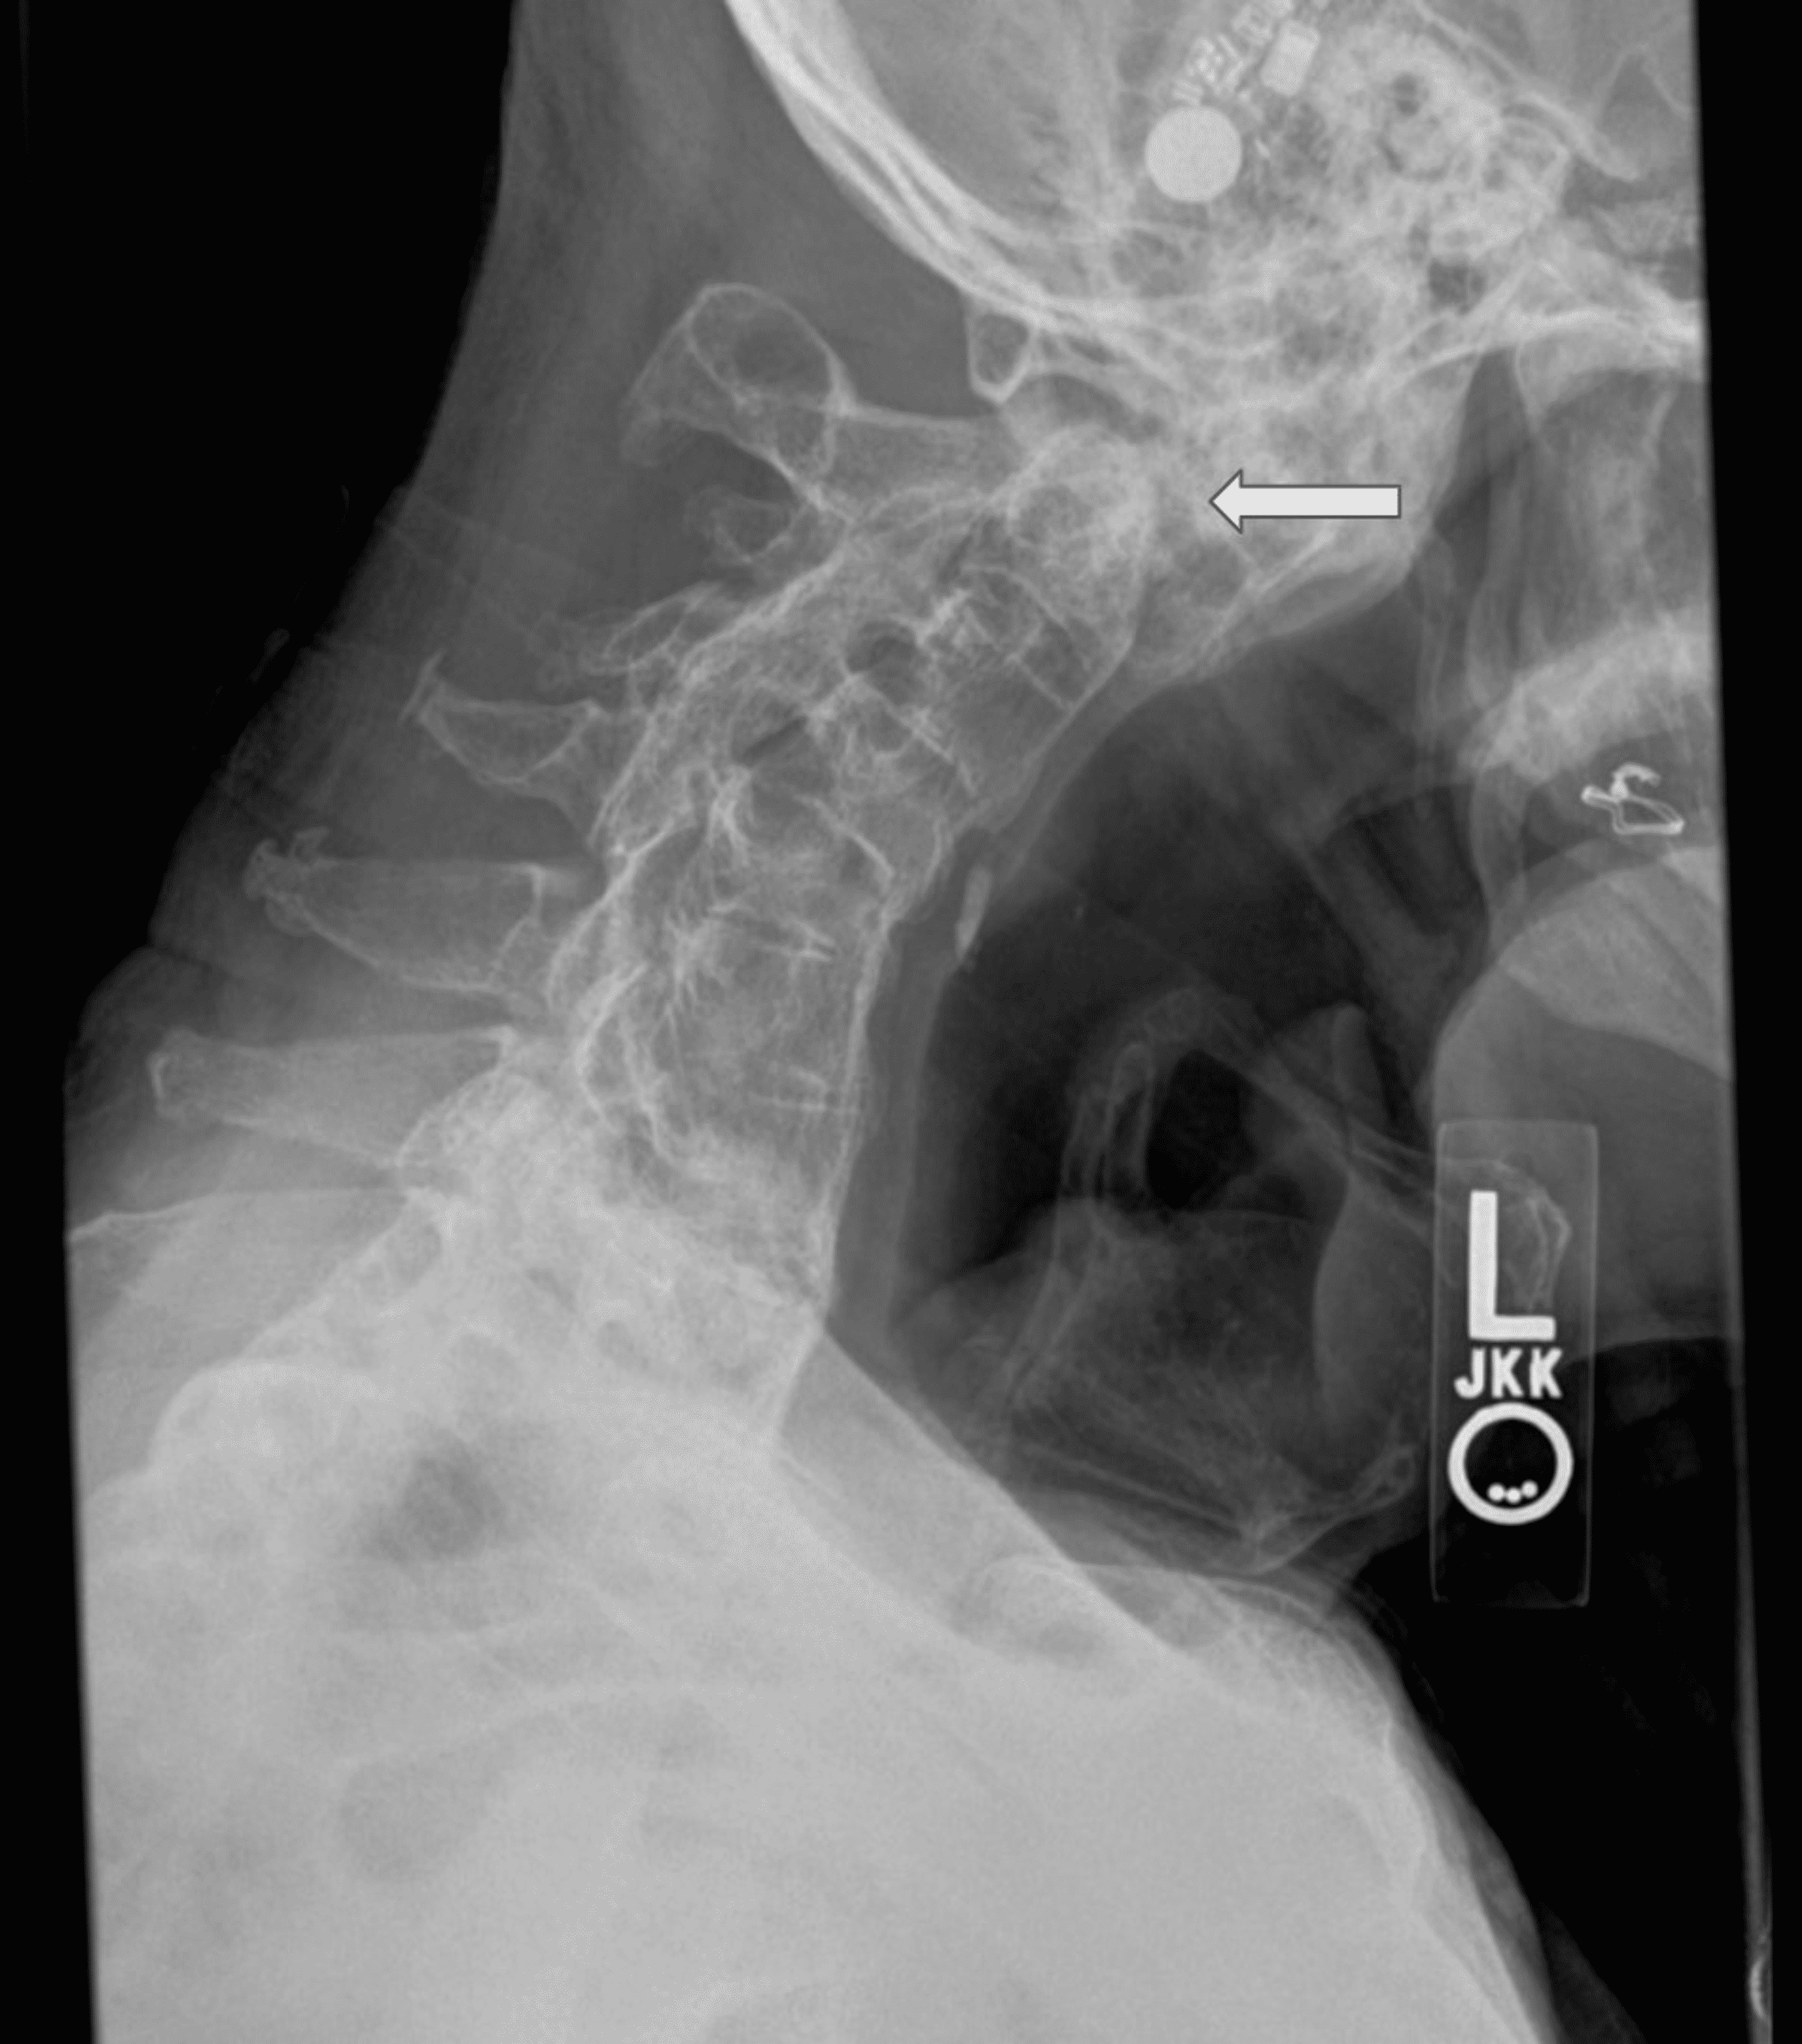

Post Operative X Ray Image Lateral Projection Showing Anterior Download Scientific Diagram

Lateral X Ray At 5 Months After The Revision Surgery Solid Fusion At Download Scientific Diagram